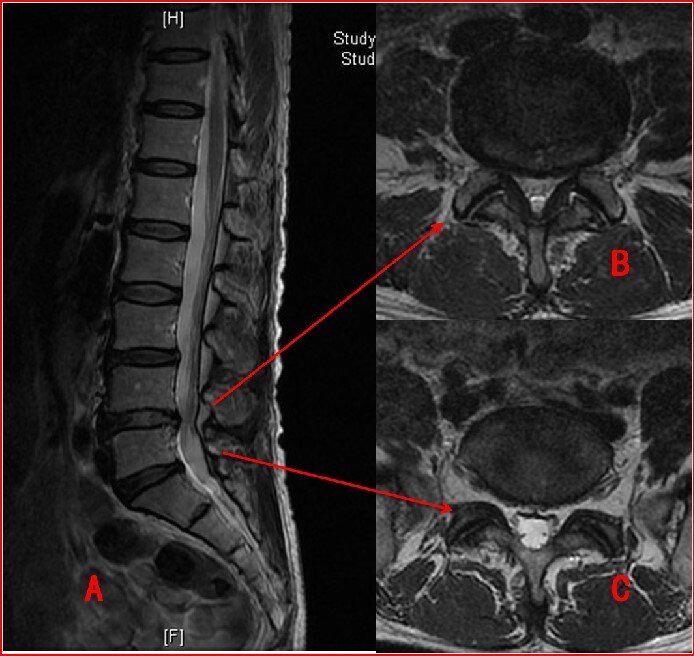

經(jīng)常有朋友愁眉苦臉的拿著CT或MRI檢查報(bào)告來(lái)門診,說(shuō)得了“腰突癥”,我看檢查報(bào)告確實(shí)寫著“腰椎間盤突出或膨出”,但通過(guò)對(duì)其問(wèn)診癥狀和檢查體征,發(fā)現(xiàn)其中多半并不能診斷為腰椎間盤突出癥(簡(jiǎn)稱腰突癥)。因?yàn)檠话Y是臨床診斷的一種病癥,而CT、MRI等影像學(xué)檢查顯示的“腰椎間盤突出或膨出”僅僅是一種影像學(xué)表現(xiàn)。每個(gè)人的脊柱隨著年齡和不良工作生活習(xí)慣多少會(huì)發(fā)生衰老退變。隨著人們年齡增長(zhǎng),脊柱退變的程度會(huì)越來(lái)越重,大部分情況下這是屬于正常的老化現(xiàn)象。只有少部分人會(huì)因?yàn)榧怪俗兌l(fā)腰腿痛,從而患上腰突癥。對(duì)于上點(diǎn)年紀(jì)的人來(lái)說(shuō),由于他們脊柱退變的發(fā)生率比較高,如果給他們做腰椎CT或者M(jìn)RI,多數(shù)都會(huì)在圖像中看到腰椎間盤突出或膨出的表現(xiàn)。但是,他很可能完全沒(méi)有任何不適,每天健康地生活著。這就不能算得了腰突癥。診斷腰突癥不僅是CT、MRI報(bào)告,還需要結(jié)合患者的癥狀和體征。癥狀包括腰痛癥狀,有時(shí)可伴有臀部疼痛和下肢放射痛,表現(xiàn)為坐骨神經(jīng)痛,嚴(yán)重者甚至出現(xiàn)馬尾神經(jīng)癥狀。體征包括一般體征和特殊體征。一般體征如腰椎側(cè)凸,腰部活動(dòng)活動(dòng)范圍受限制,腰部壓痛、叩痛及骶棘肌痙攣壓痛。特殊體征包括直腿抬高試驗(yàn)及加強(qiáng)試驗(yàn)陽(yáng)性。高位腰椎間盤突出的患者可能出現(xiàn)股神經(jīng)牽拉試驗(yàn)陽(yáng)性。其他體征還包括軀體的感覺(jué)減退、麻木、刺痛和肌力改變。醫(yī)生根據(jù)患者的臨床癥狀、體征,再結(jié)合影像學(xué)檢查結(jié)果,三者吻合才能明確診斷腰突癥;如果臨床癥狀體征明顯而影像學(xué)檢查沒(méi)有發(fā)現(xiàn)椎間盤突出或膨出,那么腰突癥的診斷也是很有可能的,因?yàn)橛跋駥W(xué)檢查并不是100%準(zhǔn)確(通常來(lái)說(shuō),CT能達(dá)到80%準(zhǔn)確率,MRI可達(dá)到95%準(zhǔn)確率);如果單純影像學(xué)檢查發(fā)現(xiàn)椎間盤突出或膨出而沒(méi)有相對(duì)應(yīng)的腰腿痛癥狀和體征,則不能診斷腰突癥,當(dāng)然有明顯的退變了我們也必須高度重視,需要注意腰椎的保養(yǎng),否則很有可能最終發(fā)展成真正的腰突癥。